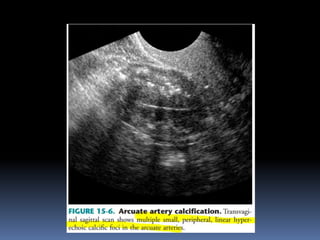

This document contains an image gallery from Dr. Mohit Goel showing various uterine anomalies and ovarian cysts. It includes images of an arcuate and unicornuate uterus, endometritis, a twisted ovarian pedicle, dermoid cysts of varying sizes and echogenicity containing hair, fat, and calcifications, and a combination dermoid cyst showing both mesh and plug structures. The gallery provides ultrasound images of different gynecological conditions for medical education and reference.